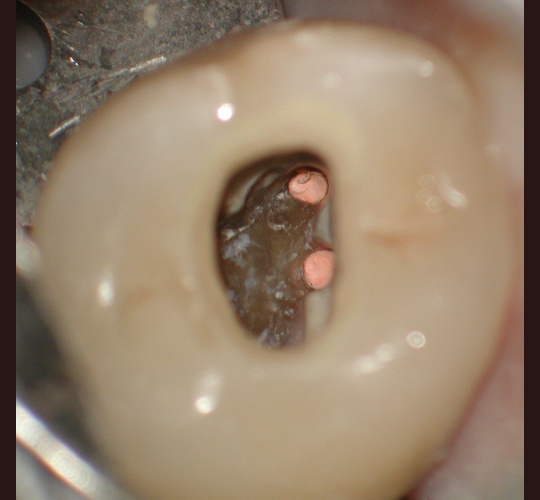

Access Closure: Case #1

When the crown is still intact and in good shape the root canal access opening can be sealed and the crown can be reused. Modern access shape outlines should not overextend and weaken the peri-cervical area. These shapes do not conform to endodontic textbook teachings. These shapes are to be done by qualified microscope using endodontic specialist.